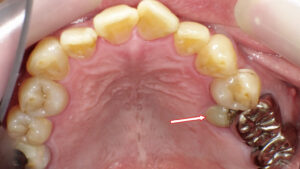

この写真では、いくつかの問題点が確認できます。

●① コンポジットレジンの変色

前歯の詰め物(コンポジットレジン)が経年劣化により、周囲の歯よりも黄ばみ・暗い色になっています。

特に矢印部分が分かりやすく、詰め物の境目がはっきりしてしまっている状態です。

●② 適合不良(段差・縁の隙間)

レジンの表面が荒れてツヤが落ちており、歯との境界に段差や隙間がある場所が見られます。

この部分はプラークが溜まりやすく、二次カリエス(詰め物の下の虫歯)につながりやすい状態です。

●③ 初期虫歯(白濁・薄い茶色の変色)

矢印の付近には、白く濁った部分や茶色い筋状の変色があり、これは“初期虫歯”の兆候です。

まだ穴は空いていない段階ですが、表面のエナメル質が弱くなり始めています。

●④ 全体的な着色

上下の前歯には、コーヒー・紅茶・タバコなどによる**ステイン(着色汚れ)**も付着しています。